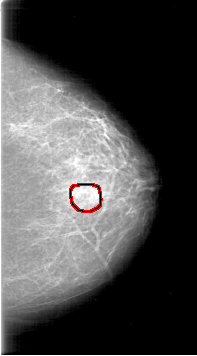

D_4189_1.RIGHT_MLO

FILE: D_4189_1.LEFT_MLO.OVERLAY

TOTAL_ABNORMALITIES 1

ABNORMALITY 1

LESION_TYPE CALCIFICATION TYPE AMORPHOUS DISTRIBUTION CLUSTERED

ASSESSMENT 0

SUBTLETY 2

PATHOLOGY MALIGNANT

TOTAL_OUTLINES 1

BOUNDARY